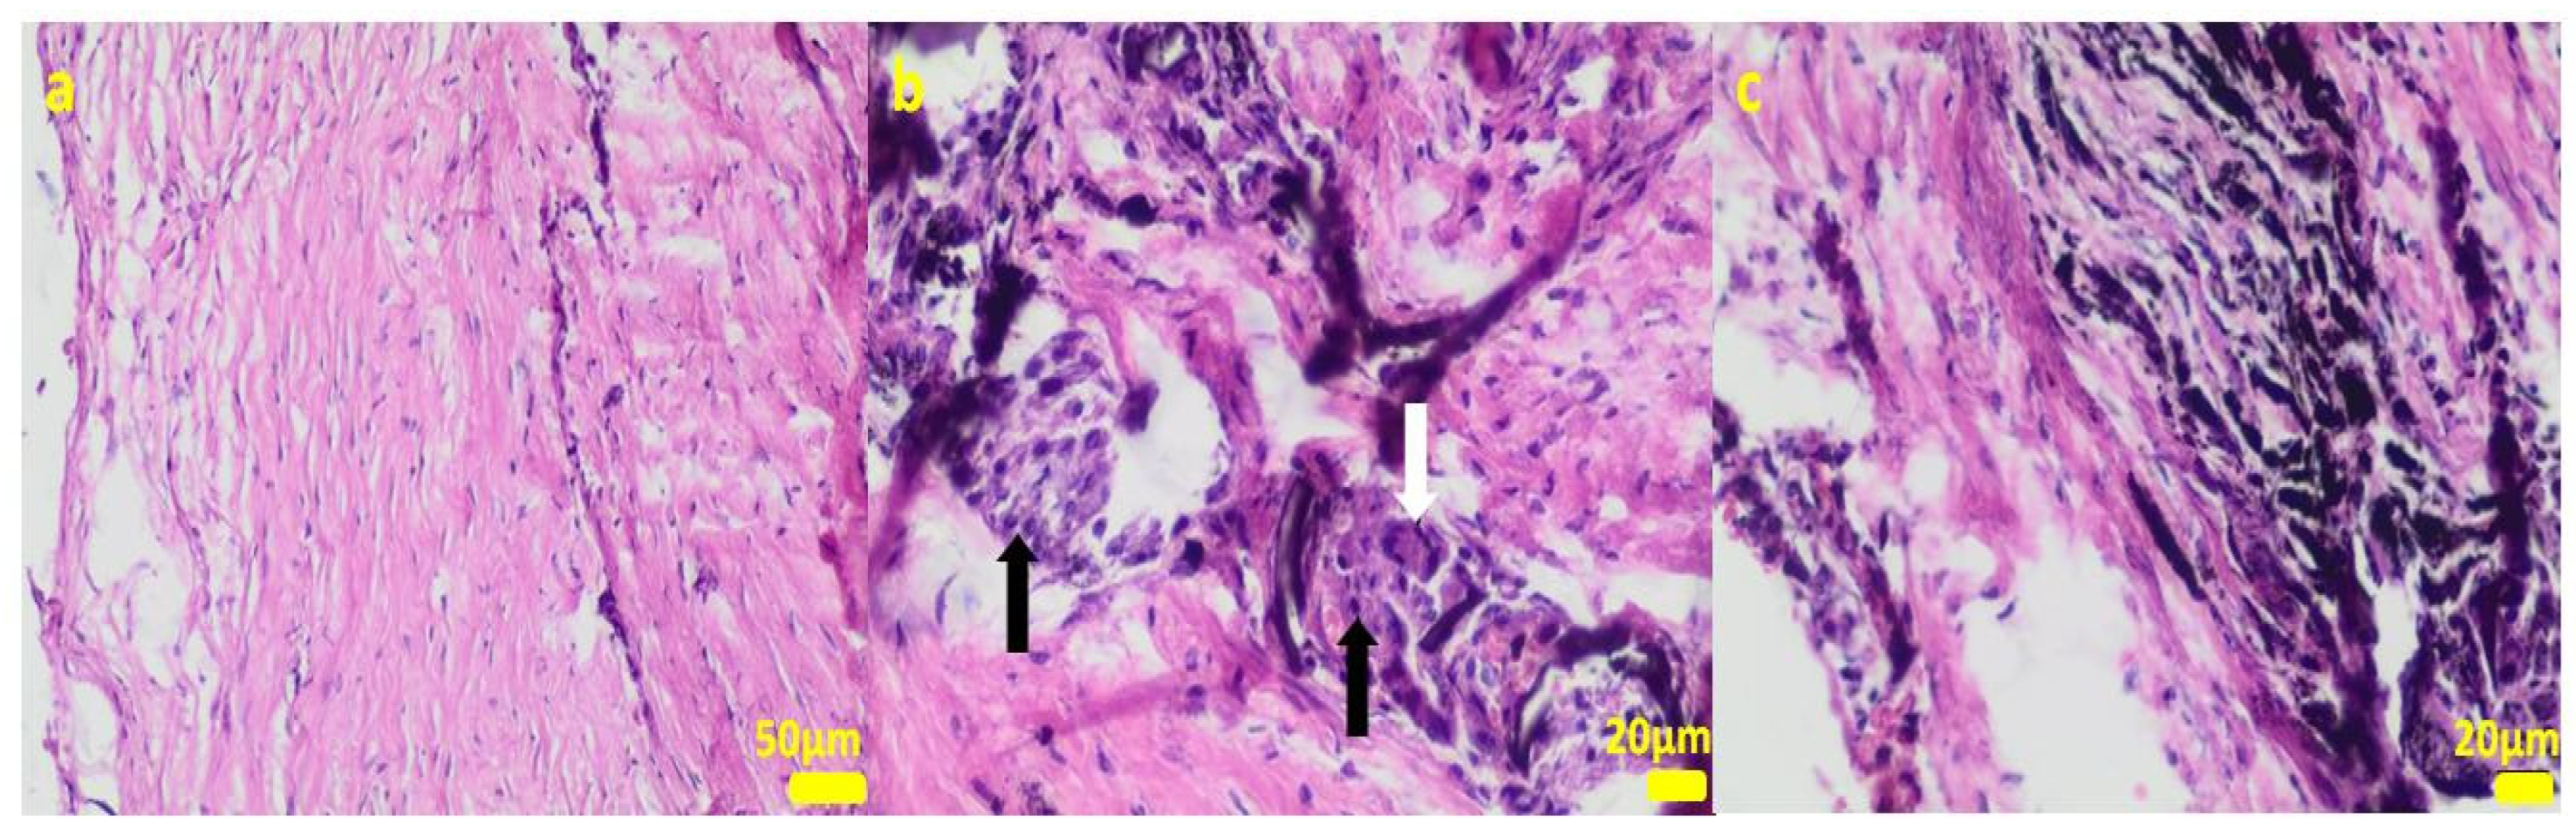

2.1. In Vitro Examinations

2.2. In Vivo Study

4.3. Cell Cultures

4.11. Histopathological Examination